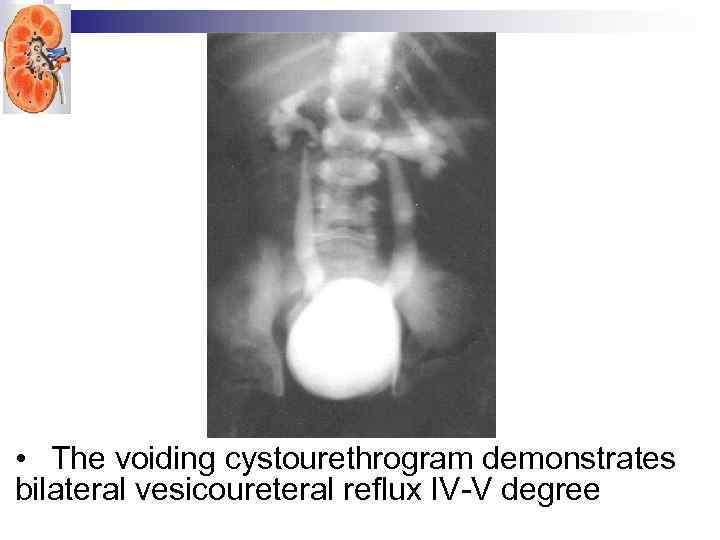

• The voiding cystourethrogram demonstrates bilateral vesicoureteral reflux IV-V degree

• The voiding cystourethrogram demonstrates bilateral vesicoureteral reflux IV-V degree